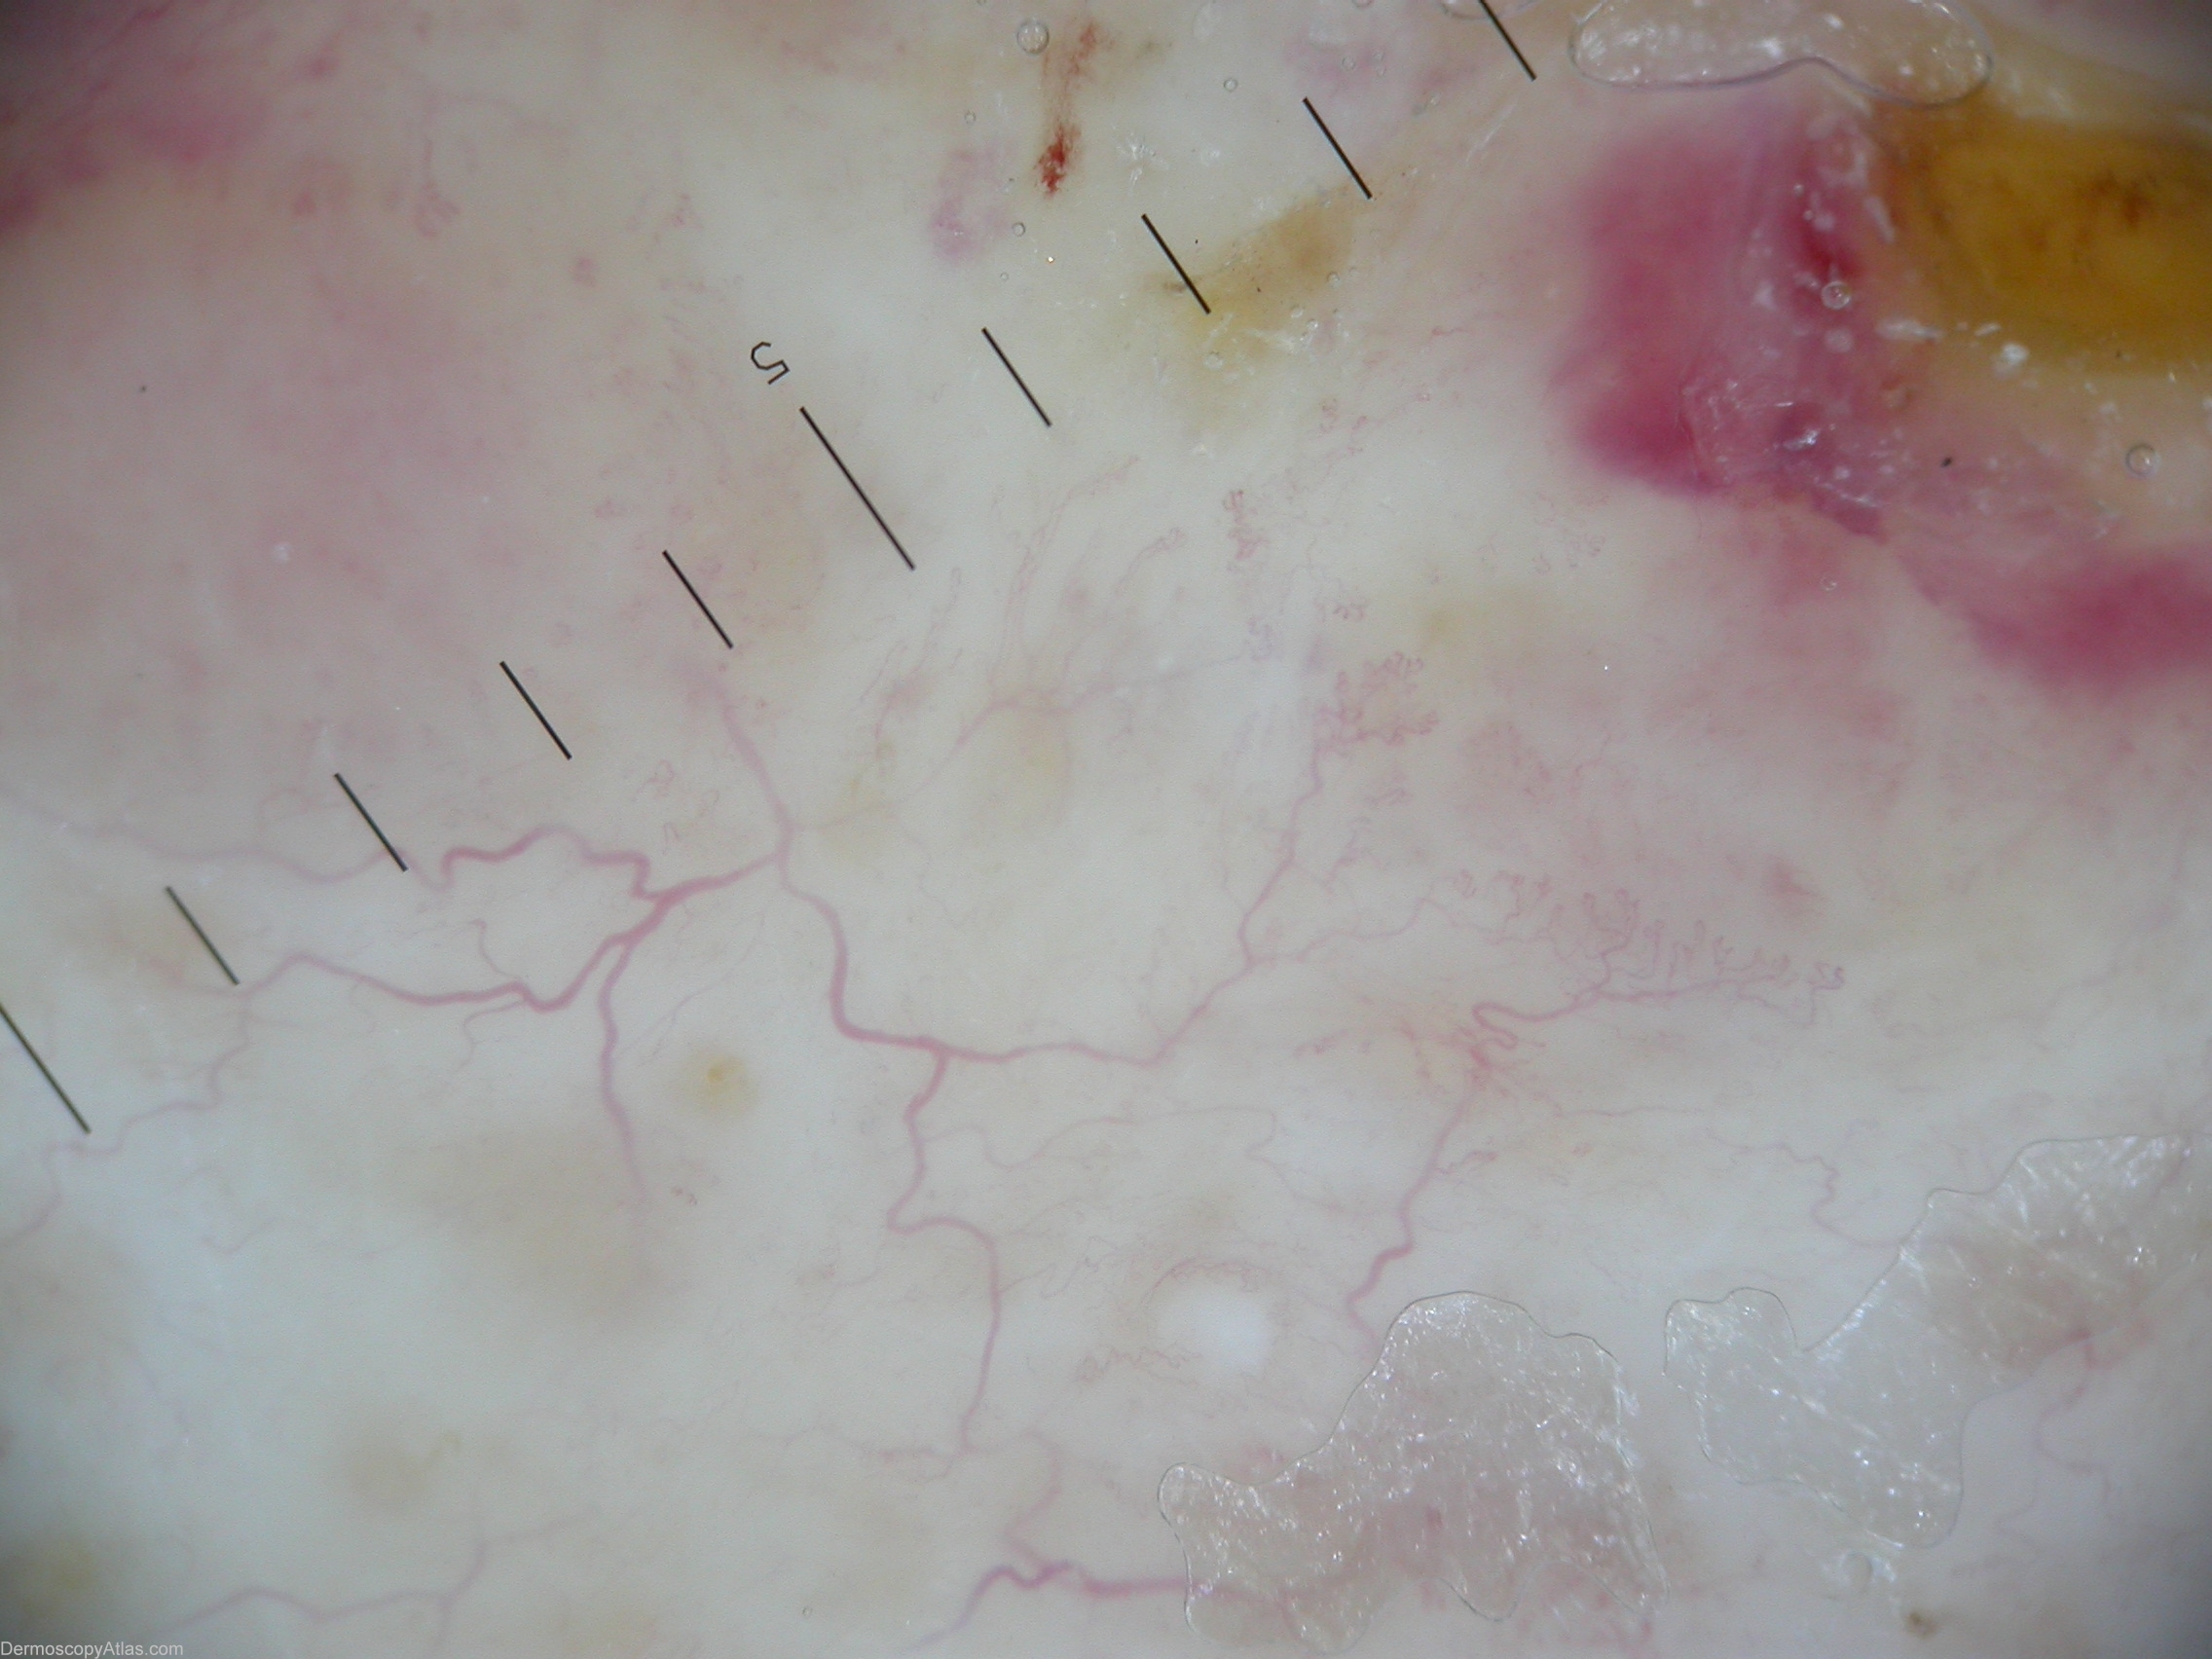

Diagnosis - Necrobiosis lipoidica

Diagnosis: Necrobiosis lipoidica